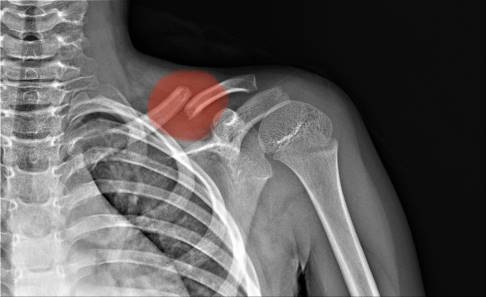

Zu Beginn der Diagnose erfolgt ein Arzt-Patienten-Gespräch, in dem der Orthopäde Ihnen Fragen über den Unfallhergang, Ihre Beschwerden und Ihre berufliche Situation stellt. Im nächsten Schritt untersucht der Arzt Ihre Schulter. Er tastet die betroffene Stelle ab und bewegt den Arm. Da das Schlüsselbein direkt unter der Haut verläuft, erkennt der Arzt einen Bruch meist schon auf einen Blick. Er achtet auf typische Symptome wie Stufenbildung, Schwellung, Hämatom und Reibegeräusche. Zudem halten Betroffene den Arm in Schonhaltung nah am Körper mit leicht nach vorne geneigter Schulter.

Um seine Verdachtsdiagnose zu bestätigen, wird der Orthopäde oder Unfallchirurg ein Röntgen veranlassen. Auf dem Röntgenbild ist in der Regel deutlich zu erkennen, an welcher Stelle und wie das Schlüsselbein gebrochen ist. Der Arzt ermittelt die Anzahl der Bruchstücke und ob diese sich gegeneinander verschoben (disloziert) haben. Dies ist wichtig für die Therapie, da gering verschobene Brüche tendenziell auch konservativ behandelt werden können. Stärker verschobene Brüche sollten eher operativ gerichtet und fixiert werden. In einigen Fällen ist zudem eine Untersuchung mittels CT notwendig. Außerdem muss der Arzt Begleitverletzungen an Gefäßen, Nerven und an der Lunge sowie Rippenfrakturen ausschließen.